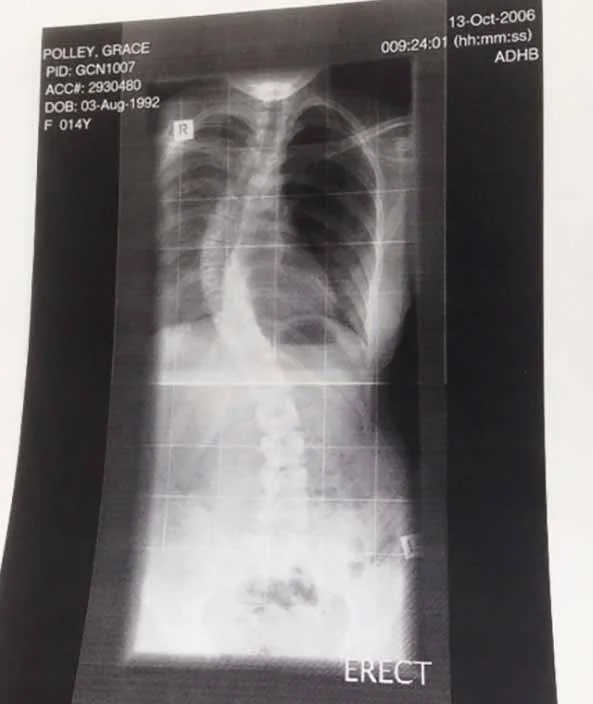

The shocked pair were told Sasha was breach and Grace needed an emergency Caesarean. Since the doting mum has rods and screws throughout her back from surgery in childhood for scoliosis – a condition that causes a curve in the spine – she went under general anaesthetic.

Grace has been told her body doesn’t show or respond to pregnancy like other females. There’s also the possibility scoliosis is the reason for the unusual placement of her ovaries.